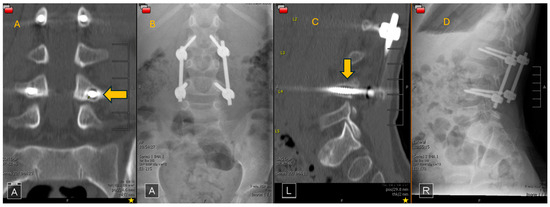

2.3. Treatment Technique

2.4. Alignment